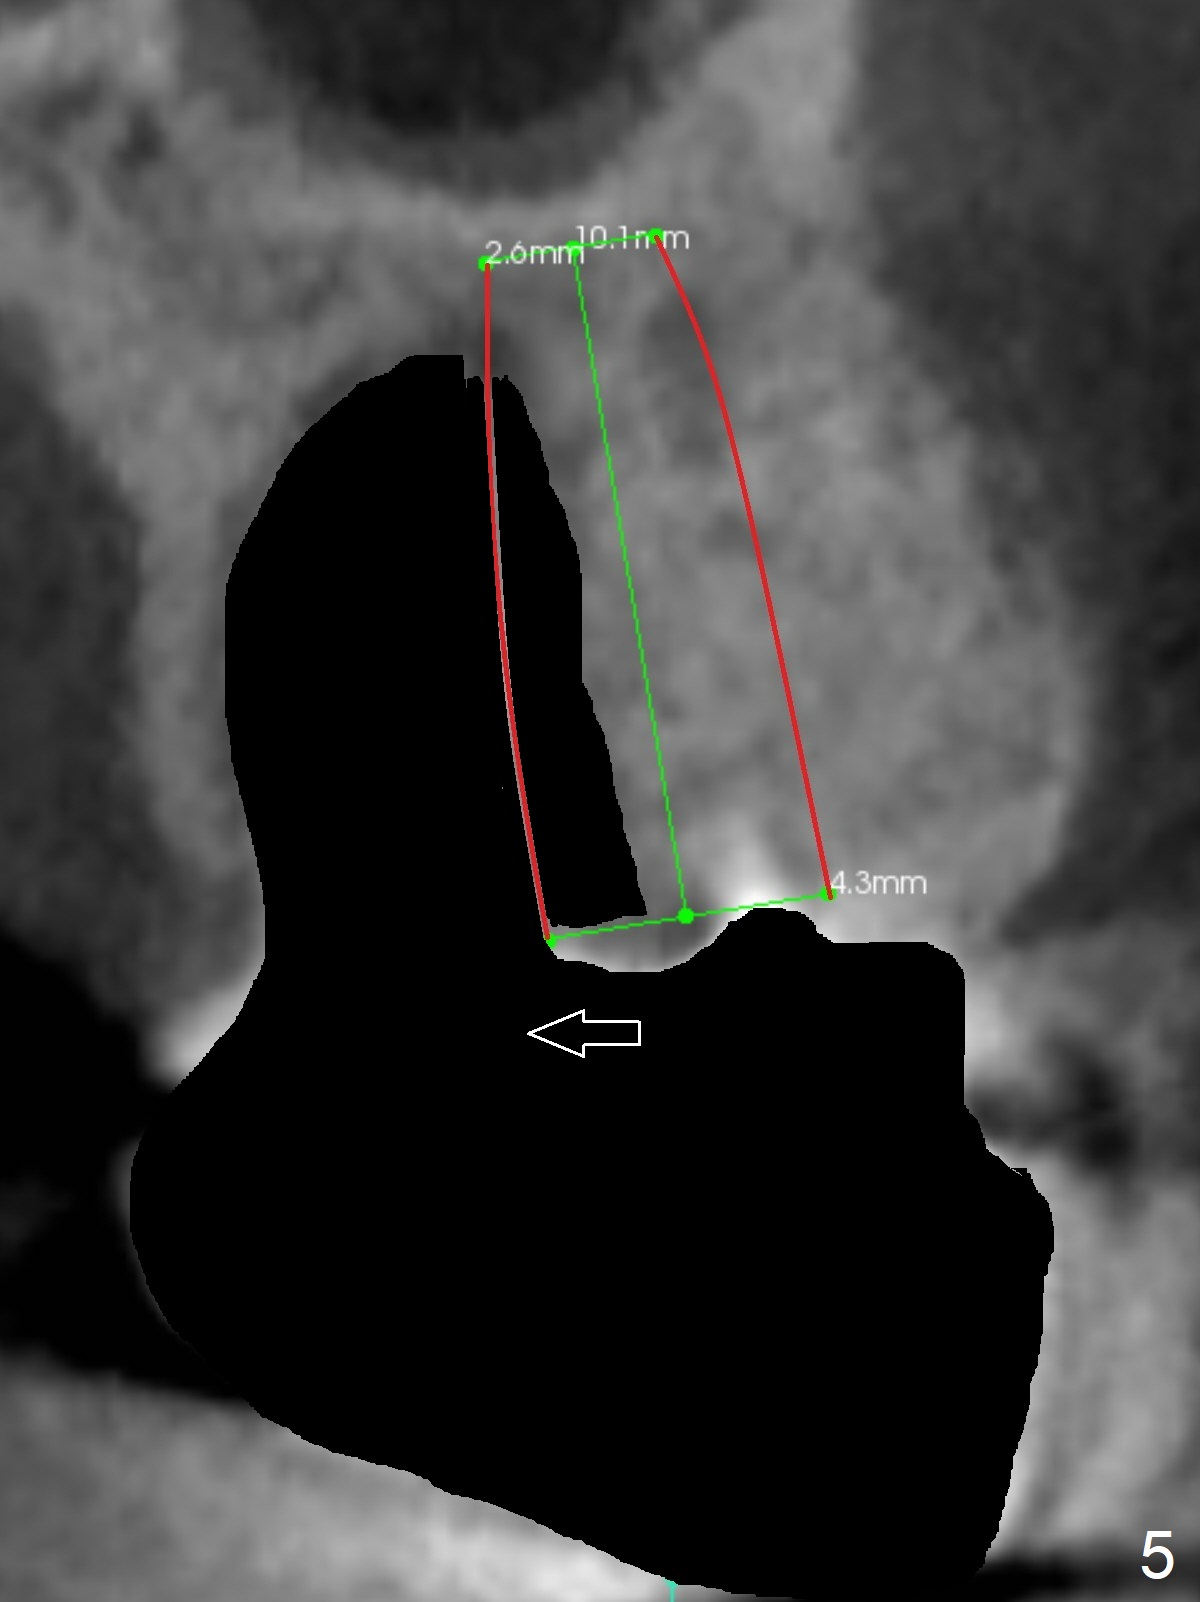

A 53-year-old man cannot chew on the left side with distal abscess in spite of RCT for #14 (* in Fig.1,2 (taken 11 ad 21 months postop, respectively)). After extraction (Fig.3 (CBCT coronal section) black area), start osteotomy with 2 mm drill (red outline) in the septum buccal to the palatal (P) socket). Following 2 mm drill removal (Fig.4), use 4.3 mm Magic Drill (red outline) for ~ 9 mm. When the osteotomy is being done, the osteotomy most likely shifts palatal (Fig.5 arrow) because of thin bone palatally. When the MD is removed (Fig.6), use Magic Sinus Lifter (Fig.7 pink) for sinus lift (arrow). The implant is to be 5x11 mm or larger. Because of the distal defect (Fig.1,2), start osteotomy mesially. Take Alginate impression before surgery for possible orthodontic treatment. Since bone density is high, use higher voltage and longer time for X-ray.